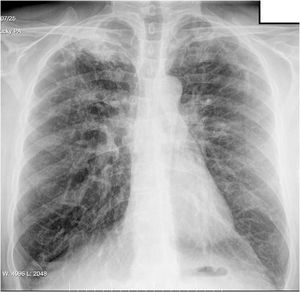

He reported having had a cough for eight months, which was initially dry, but with purulent sputum in the previous few days, although no haemoptysis. He had no pyrexia, constitutional syndrome or apparent contact with individuals with respiratory disease. Chest X-ray showed right apical infiltrate (Fig. 1) and sputum smear microscopy was positive.